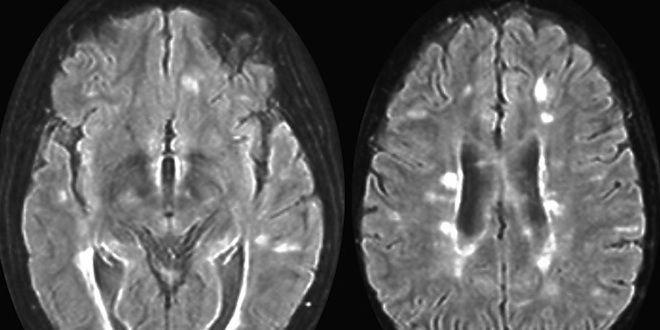

Cette maladie provoque un dérèglement du système immunitaire, lequel s'attaque à la myéline, la gaine protectrice des fibres nerveuses. Le plus souvent, elle se manifeste par des poussées inflammatoires entrecoupées de phases d'accalmie pendant lesquelles la myéline se reconstitue en partie. Les symptômes de la maladie sont variés : faiblesse musculaire, troubles de l'équilibre, de la vision, du langage, paralysies. A plus ou moins long terme, un handicap irréversible peut s'installer.

Les traitements apparus depuis une vingtaine d'années améliorent la qualité de vie des patients et, grâce aux progrès de l'imagerie, le diagnostic, et donc la prise en charge, sont plus précoces qu'avant.